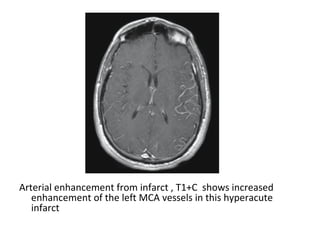

Arterial enhancement from infarct , T1+C shows increased

enhancement of the left MCA vessels in this hyperacute

infarct